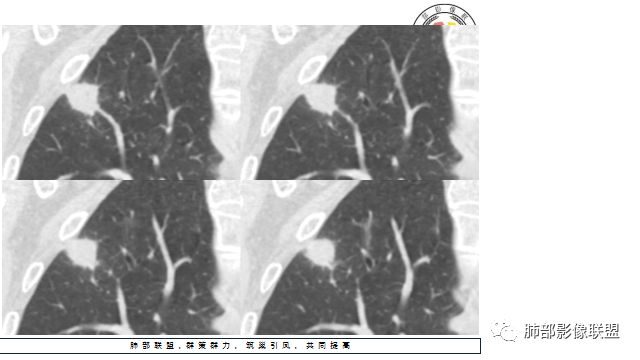

晨读:患者中老年男性,咳嗽 咳痰伴痰中带血2天,发现右上肺结节入院。

胸CT:右上肺结节,病灶位于胸膜下,边缘可见平直 u型征 软毛刺 晕,增强可见延迟强化,病灶中心低密度区。

2.右肺尖类圆形结节影,边界清楚,未见明显分叶或深切迹,部分分边缘较平直,可见细长毛刺棘状突起,相邻胸膜增厚,未见胸膜凹陷。后段胸膜下见条索影及微小结节影。

相关血管未见脐凹,有限图像层面未能显示相关支气管情况。